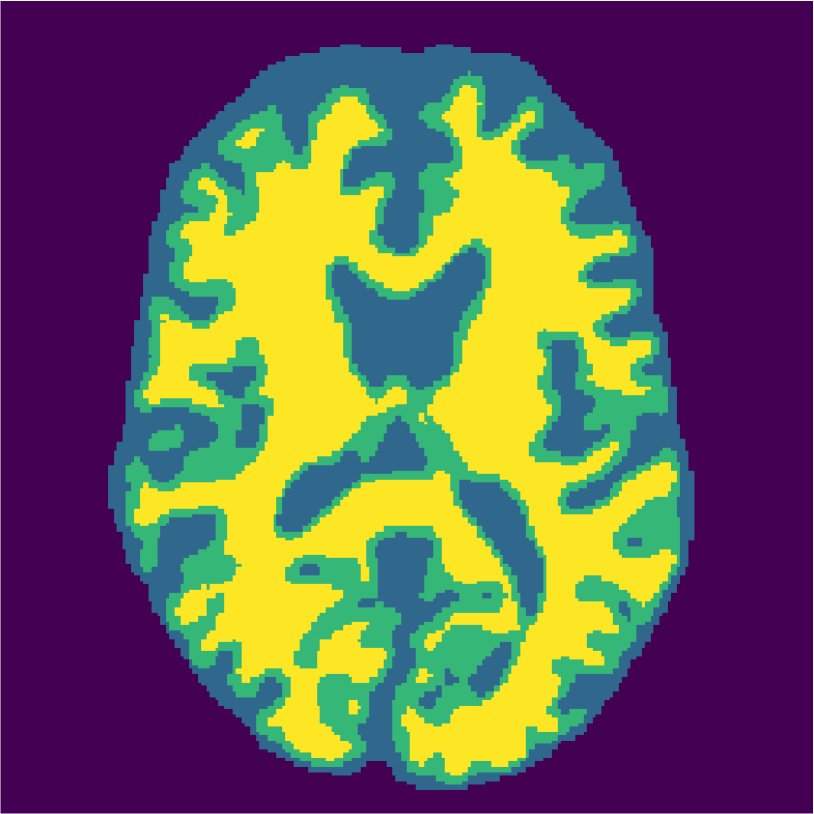

Figure 6 displays the manually selected patches and their position within the image. For both the source and target classifier, one target patch per tissue is insufficient to achieve good tissue classification performance (2 (top row): 0.631 and 0.613). However, the mrai-net classifier shows considerably better performance (0.223), using only one target patch per tissue. The proxy -distance also drops from near perfect separability (1.88) to near invariance (0.26). Randomly selecting (10 repeats) 1 target patch per tissue (Table 2 (bottom row)), shows worse performance of the mrai-net classifier, for both the classification error (0.250) as well as the -distance (0.41). Suggesting that purposive (information rich) sampling beats random sampling in this case.

Examples of the segmentation results on one of the target test images are shown in Figure 8 for experiment 2.1, Figure 9 for experiment 2.2, and Figure 10 for experiment 2.3. Examples are shown after using 1 target patch per tissue for training, and after using 100 target patches per tissue for training. The results show that only the mrai-net classifier is able to predict a segmentation that approaches the ground truth with only 1 target patch per tissue for training (error for experiment 2.1 = 0.269, experiment 2.2 = 0.403, experiment 2.3 = 0.320), while the source and target classifiers cannot (source error for experiment 2.1 = 0.667, experiment 2.2 = 0.653, experiment 2.3 = 0.435; target error for experiment 2.1: 0.591, experiment 2.2: 0.614, experiment 2.3 = 0.596). After using 100 patches the source and target classifiers can predict a gross segmentation of WM, GM and CSF (source error for experiment 2.1 = 0.213, experiment 2.2 = 0.384, experiment 2.3 = 0.363; target error for experiment 2.1: 0.205, experiment 2.2: 0.368, experiment 2.3 = 0.368), but the mrai-net classifier prediction shows more details and a lower tissue classification error (error for experiment 2.1 = 0.111, experiment 2.2 = 0.276, experiment 2.3 = 0.284).